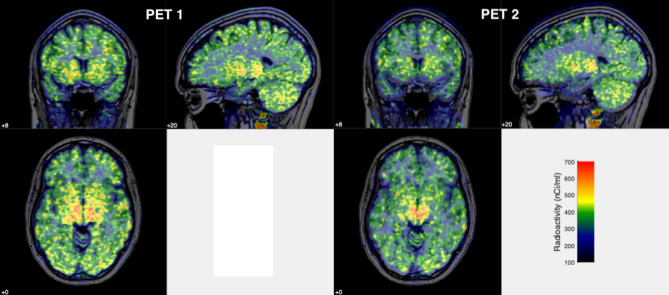

Test-retest properties of [11C]PXT012253 as a positron emission tomography (PET) radiotracer in healthy human brain: PET imaging of mGlu4.